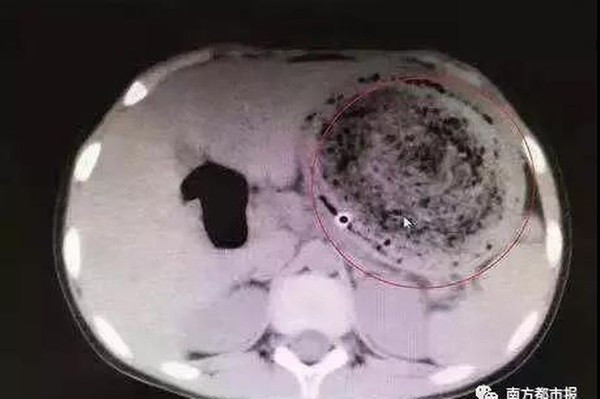

Bác sĩ đã rất ngạc nhiên khi chụp CT và phát hiện một búi tóc khổng lồ lẫn với cặn thức ăn. Tuy nhiên, búi tóc to bằng quả bóng này không thể được loại bỏ thông qua nội soi vì có dấu hiệu vôi hóa.

| Hình ảnh búi tóc rối trong dạ dày của Phi Phi. |

Cuối cùng, bác sĩ Tang phải tiến hành phẫu thuật, lấy “quả bóng tóc” nặng 1,5 kg ra khỏi dạ dày của Phi Phi.